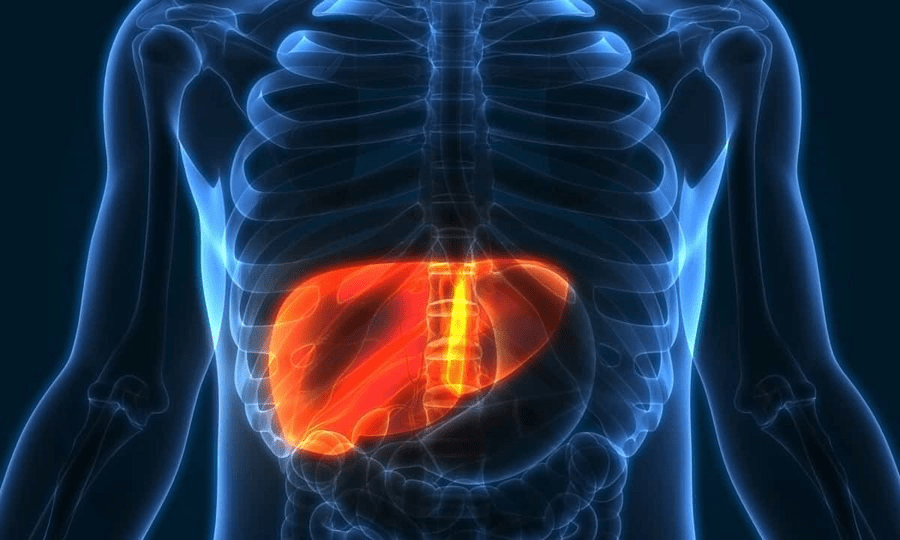

Një dietë e kufizuar me kalori dhe jo me proteina të ulëta çoi në një reduktim prej 40% të yndyrës së akumuluar në mëlçi, sipas gjetjeve të një studimi gjerman që ekzaminoi efektin e modelit dietik në sëmundjen e mëlçisë yndyrore joalkoolike, shkaku më i zakonshëm i sëmundjeve kronike të mëlçisë në mbarë botën. Ekipi hulumtues i Institutit Gjerman të Ushqyerjes Potsdam-Rehbruecke (DifE), i udhëhequr nga Dr. Olga Ramich dhe profesori Andreas Pfeiffer, kishin identifikuar tashmë në studimet e mëparshme se një dietë me proteina të lartë është më efektive se ajo me pak proteina, dhe në një studim të ri, i botuar në Liver – tani hedh dritë mbi mekanizmin e funksionimit të kësaj diete të veçantë. Sëmundja e mëlçisë dhjamore jo-alkoolike karakterizohet nga grumbullimi i yndyrës në mëlçi dhe shpesh shoqërohet me obezitet, diabetin e tipit 2, presionin e lartë të gjakut dhe çrregullimet e lipideve. Nëse nuk trajtohet, mbart rrezikun e zhvillimit të cirrozës së mëlçisë dhe mund të kërcënojë jetën e të sëmurit. Shkaqet e sëmundjes variojnë nga një mënyrë jetese jo e shëndetshme, ngrënia e shumë ushqimeve me shumë yndyrë dhe sheqer, si dhe mungesa e ushtrimeve fizike, deri te faktorët gjenetikë.

Në studimin e ri, studiuesit shikuan se si përmbajtja e proteinave në ushqime ndikon në sasinë e yndyrës së mëlçisë tek njerëzit obezë me sëmundje të mëlçisë yndyrore jo-alkoolike. Nëntëmbëdhjetë pjesëmarrës ndoqën një dietë me proteina të lartë ose të ulët për tre javë. Ata më pas iu nënshtruan një operacioni bariatrik për të trajtuar obezitetin gjatë të cilit u morën mostrat e mëlçisë, shkruan TCH. Analiza e mostrave tregoi se dieta me kalori të ulët dhe me shumë proteina reduktoi yndyrën e mëlçisë në mënyrë më efektive sesa dieta me kalori të ulët dhe me proteina të lartë. Në rastin e parë sasia e yndyrës u reduktua me 40%, ndërsa në rastin e dytë mbeti e pandryshuar. Pjesëmarrësit në të dy grupet humbën gjithsej rreth pesë kilogramë.“Nëse rezultatet vazhdojnë të konfirmohen në studime më të mëdha, rekomandimi për rritjen e marrjes së proteinave të kombinuara me një dietë të shëndetshme me pak yndyrë mund të gjejë rrugën e saj në mjekësi si pjesë e një trajtimi efektiv për mëlçinë e dhjamosur”, thotë Andreas Pfeiffer.

Studiuesit vlerësojnë se efekti pozitiv i kësaj diete qëndron kryesisht në faktin se marrja, ruajtja dhe sinteza e yndyrës është e shtypur. Kjo sugjerohet nga analizat gjenetike të gjera të mostrave të mëlçisë të kryera më pas nga profesori Stephan Herzig dhe ekipi i tij në qendrën kërkimore Helmholtz Zentrum München. Bazuar në këto analiza, disa gjene përgjegjës për thithjen, ruajtjen dhe sintezën e yndyrës në mëlçi ishin më pak aktive pas dietës me proteina të lartë sesa pas dietës së ulët. Në të njëjtën kohë, me rezultate befasuese u hetuan edhe mitokondritë, sipas Dr. Olga Ramich, e cila kreu studimin përkatës së bashku me kolegët e saj në Departamentin e Fiziologjisë dhe Metabolizmit të Energjisë të Institutit Gjerman të Ushqyerjes Potsdam-Rehbruecke. “Aktiviteti mitokondrial ishte shumë i ngjashëm në të dy grupet. Kjo na befasoi. Fillimisht të hidhnim hipotezën se një dietë me proteina të lartë do të rriste aktivitetin mitokondrial dhe kështu do të kontribuonte në reduktimin e yndyrës së mëlçisë”, tha Susanne Klaus, kreu i Departamentit të Fiziologjisë dhe Metabolizmit të Energjisë. Studiuesit u befasuan gjithashtu kur zbuluan se nivelet serike të faktorit të rritjes së fibroblasteve 21 ishin më të ulëta pas dietës me proteina të lartë që reduktonte yndyrën e mëlçisë sesa pas dietës me pak proteina.